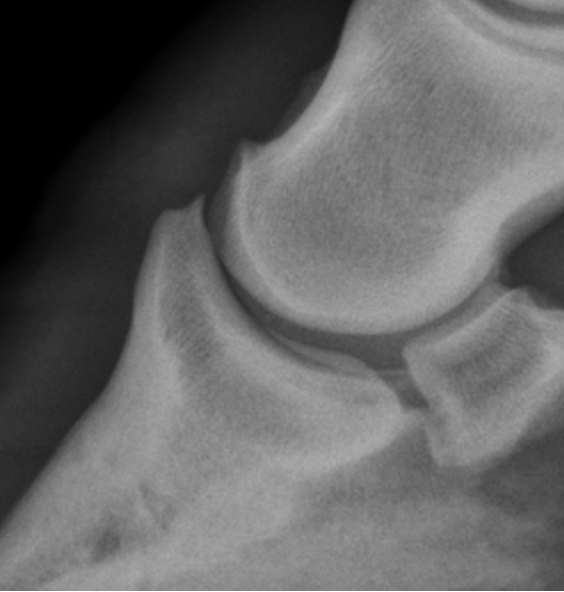

navicular degeneration signs

synovial invaginations on distal border

abnormal margins

cyst like lesions

sclerotic

erosion of flexor surface

navicular degeneration

navicular osteomyelitis signs

penetrating wound

fistulography with draining tract

toe touching lame that is resolved with nerve block

lysis and sclerosis of flexor surface

navicular osteomyelitis